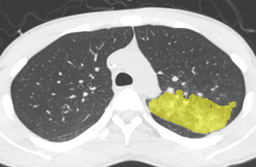

In this paper, we define partial annotation as an annotation format in which only one class is chosen for the annotation and only pixels belonging to the chosen class are annotated per image. For example, in Figure 1(a), although there is ground glass opacity in the image, only consolidation is chosen for annotation and pixels of consolidation are annotated. Partially annotated dataset is less informative for training, however, it is much easier to create compared to fully annotated dataset since annotators only need to focus on one class at a time during the annotation task.

Statistics of our dataset are shown in Table 1 and typical images and their annotations for each DLD pattern are shown in Figure 1. In our partially annotated dataset, all the pixels in a slice were manually classified into two classes: dominating DLD pattern and other tissues. In other words, all the pixels in our dataset were assigned one of the labels from either of the two label sets, Lstrong={lCON,lGGO,lHCM,lEMP,lNOR}subscript𝐿𝑠𝑡𝑟𝑜𝑛𝑔subscript𝑙𝐶𝑂𝑁subscript𝑙𝐺𝐺𝑂subscript𝑙𝐻𝐶𝑀subscript𝑙𝐸𝑀𝑃subscript𝑙𝑁𝑂𝑅L_{strong}=\{l_{CON},l_{GGO},l_{HCM},l_{EMP},l_{NOR}\} or Lweak={lCON¯,lGGO¯,lHCM¯,lEMP¯,lNOR¯}subscript𝐿𝑤𝑒𝑎𝑘subscript𝑙¯𝐶𝑂𝑁subscript𝑙¯𝐺𝐺𝑂subscript𝑙¯𝐻𝐶𝑀subscript𝑙¯𝐸𝑀𝑃subscript𝑙¯𝑁𝑂𝑅L_{weak}=\{l_{\overline{CON}},l_{\overline{GGO}},l_{\overline{HCM}},l_{\overline{EMP}},l_{\overline{NOR}}\}. For example, in Figure 1(a), colored pixels were labeled as lCONsubscript𝑙𝐶𝑂𝑁l_{CON} and all the other pixels were labeled as lCON¯subscript𝑙¯𝐶𝑂𝑁l_{\overline{CON}}. In this paper, we call pixels of label lLweak𝑙subscript𝐿𝑤𝑒𝑎𝑘l\in L_{weak} and lLstrong𝑙subscript𝐿𝑠𝑡𝑟𝑜𝑛𝑔l\in L_{strong} as weakly annotated pixels and strongly annotated pixels respectively. Our pixel-wise annotations were created in the following steps. First, up to 3 slices were chosen for the annotation for each HRCT scan and for each slice, one representing DLD pattern was chosen by a radiologist. Second, three radiologists performed pixel-wise binary annotation (e.g. binary annotation between lCONsubscript𝑙𝐶𝑂𝑁l_{CON} or lCON¯subscript𝑙¯𝐶𝑂𝑁l_{\overline{CON}}) for each slice. Finally, the radiologists’ annotations were merged by taking majority classes for each pixel (i.e. pixels labeled as a DLD pattern by more than 2 radiologists became the corresponding DLD pixel). In addition to the DLDs annotation, lung fields were manually segmented under the supervision of radiologists and training and testing were conducted only within the lung fields.

Figure 1: Typical slices for each DLD classes. Slices of HRCT are shown in lung window setting (window-center=-600, window-width=1500) with annotated labels superimposed in transparent colors. Note that even if more than one DLD patterns existed, only one DLD pattern was chosen and annotated for a slice to facilitate the annotation process.